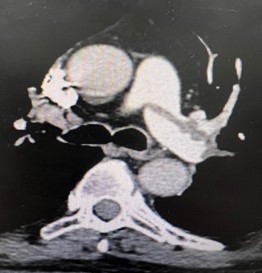

All patients were submitted to a preoperative pulmonary CT-SCAN, showing a large thrombus burden at main pulmonary arteries (figures 3 and 4).

Figure 3: CT-Scan demonstrating large thrombus burden at left pulmonary artery